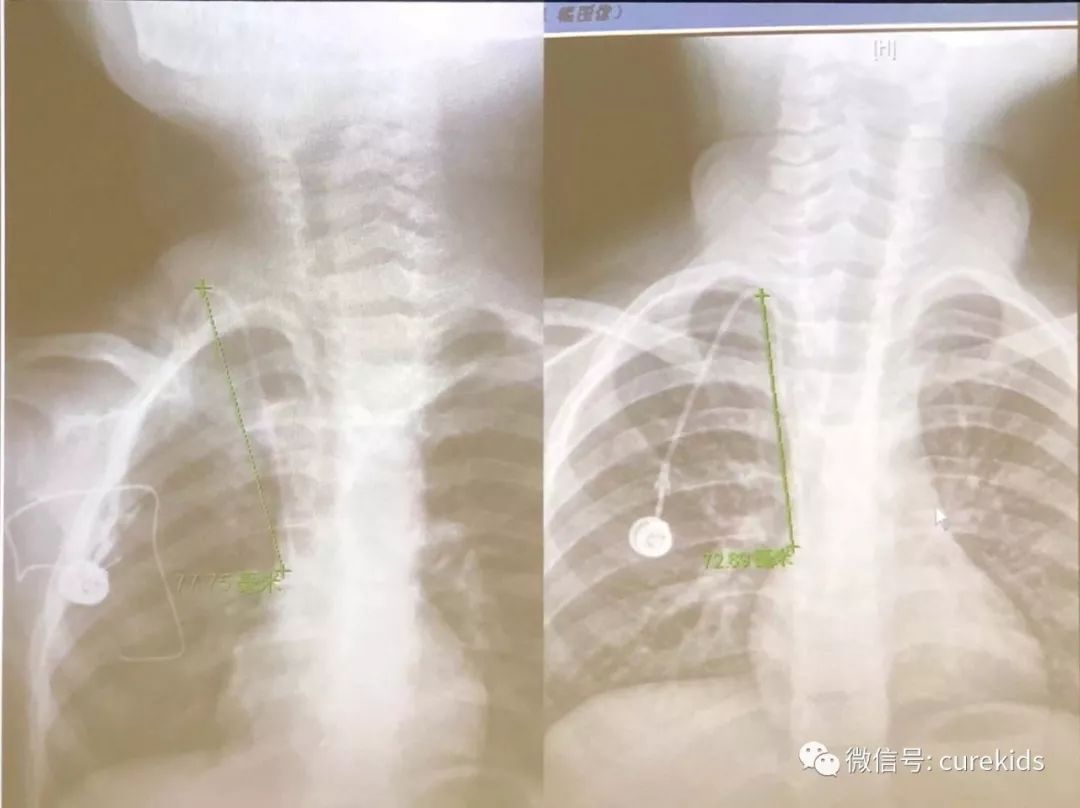

在临床实践中,我们曾发现一位患儿,置管时导管尖端在t7靠近右心房处,结疗后取港时,身高增长9 cm,胸片显示输液港导管尖端仍在t7,经过测量计算出导管尖端外移4.86 mm。但是导管尖端仍在上腔静脉内,可以正常使用。这个数据可以参考(见下图)。

我们临床曾发现有一位患儿,置管时显示导管尖端在t7靠近右心房处,结疗后取港时,身高增长9公分,胸片显示输液港导管尖端仍在t7,测量发现导管尖端外移了4.86 mm,但是导管尖端仍在上腔静脉内,可以正常使用。这个数据可以参考(见问题4图片)。如果留置期间在常规维护的过程中有任何不适,应及时就诊。